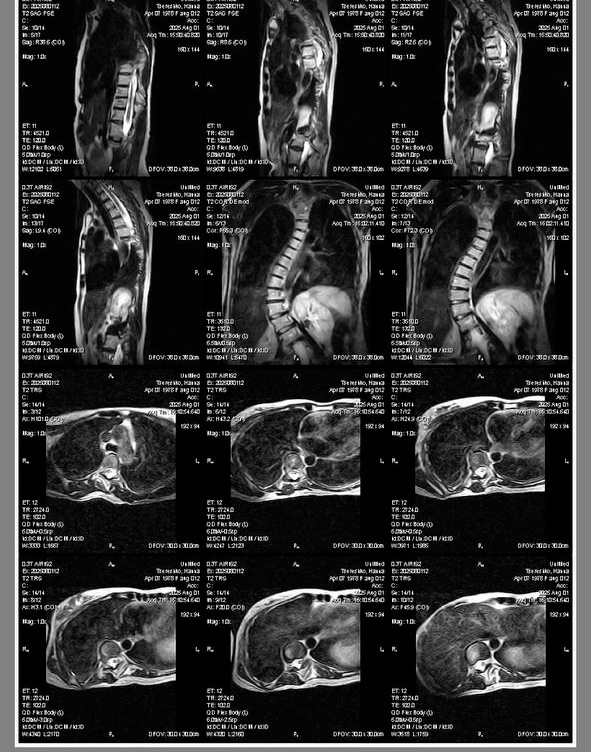

Діагноз: Ідіопатична сколіотична деформація хребта в дорослому віці. Правобічний реберний горб.

Сколіотична деформація хребта — це не лише викривлення спини.

У дорослому віці тяжкий сколіоз часто продовжує прогресувати на 1–3° щороку, поступово руйнуючи хребет.

Лікарі рекомендують складну операцію:

Корекція сколіотичної деформації (категорія 4)

• 20–25 титанових імплантів

• система Medtronic / NovaSpine

• 14 днів госпіталізації

Під час операції хірурги встановлюють спеціальні гвинти і стрижні, які вирівнюють і стабілізують хребет.